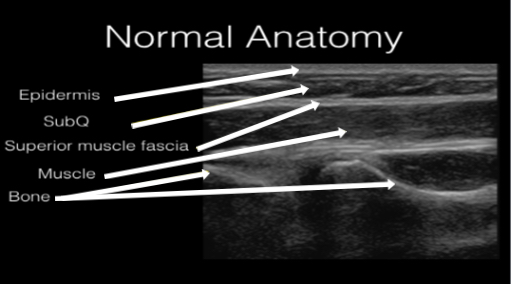

Figure 1 demonstrates normal appearing layers of soft tissue, fascia, muscle and bone. In general, the epidermis, fascia, and bone are hyperechoic compared to subcutaneous fat and muscle (which are hypoechoic). Bone will typically produce a clean shadow. Figure 2 demonstrates normal bony cortex in a long axis with shadow below. Muscle in a short axis is mostly hypoechoic with a few hyperechoic portions (Figure 3). In the long axis you can appreciate muscle fiber striations (Figure 4). Tendon in a long axis appears as a thin, well demarcated structure with striated fibers (Figure 5). Figure 6 demonstrates the principle of anisotropy, which is most apparent when imaging tendons and muscles. Muscle and tendon may appear focally hypoechoic depending on the angle of the transducer, but this is artefactual and will disappear with further interrogation. Figure 7 demonstrates a normal shoulder joint with no anechoic effusion and normal articulation of the glenoid and the humeral head.

Figure 1. Normal soft tissue, muscle, fascia, and bone layers on gray scale ultrasound.